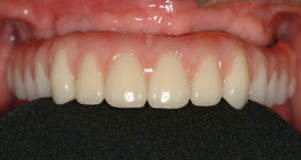

最低4本のインプラントを埋入し、それらを連結し、半日で固定式の仮歯まで入れて審美性、機能性を一日でとりもどせる革新的な治療。

2.歯の形はほぼ天然歯があった時と同じになるので取り外しの義歯に比べて違和感がなく、手入れもインプラントの本数を少なくすることにより、清掃もし易くなっています。